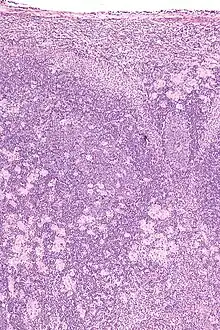

Fundus image of choroidal neovascularization in ocular toxoplasmosis

Infection of the vitreous body in toxoplasmosis of the eye